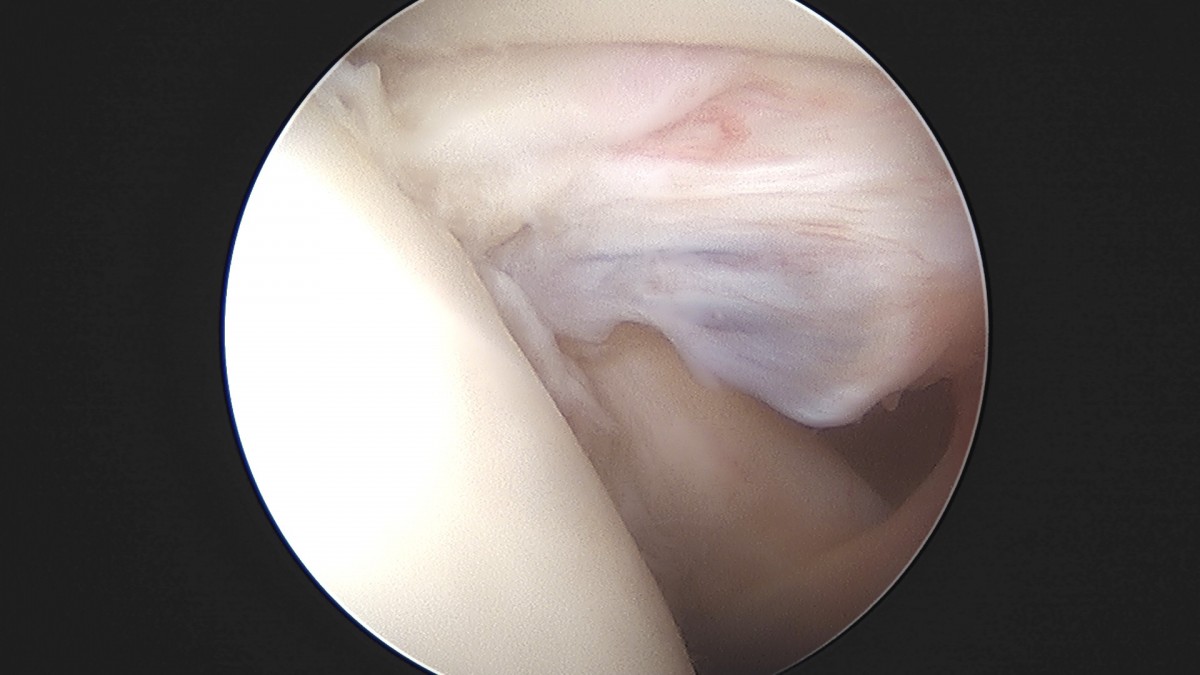

정지영원장님 어깨 관절낭 이완술 이상O 환자

dae765e4d9ac96aee867c9d6292d8784_1758009481_0942.jpg